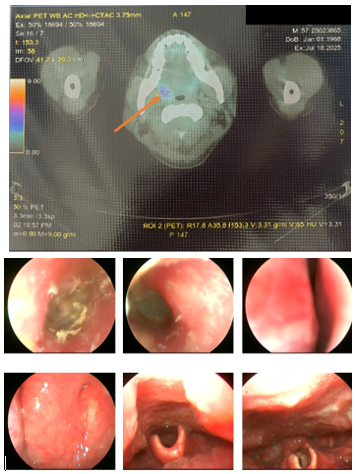

Nội soi thực quản - dạ dày: Viêm dạ dày trào ngược dịch mật. Chưa phát hiện tổn thương nghi ngờ ác tính.

Nội soi đại tràng: Hình ảnh nội soi đại trực tràng bình thường. Trĩ độ I. Chưa phát hiện tổn thương nghi ngờ ác tính

Nội soi tai mũi họng: Nấm ống tai ngoài bên trái. Chưa phát hiện tổn thương nghi ngờ ác tính các vùng khoang mũi, miệng, họng, thanh quản, ống 2 bên.

Hình 2. Hình ảnh tăng chuyển hóa FDG ở amidam bên phải với SUVmax: 3.71 (được ký hiệu bằng mũi tên màu da cam, hình trên). Tuy nhiên, khi đối chiếu với hình ảnh nội soi tai mũi họng lại không có tổn thương nghi ngờ ác tính (Hình dưới).

Hình 6. Hình ảnh nội soi tai mũi họng chưa phát hiện tổn thương nghi ngờ ác tính (Tai Phải: Ống tai ngoài có mảng trắng dạng nấm, Màng nhĩ dày đục; Tai trái: Màng nhĩ dày đục; Mũi: Khe sàn mũi sạch, cuốn mũi 2 bên bình thường; Vòm họng: Nhẵn, sạch, cân đối; Họng: Sạch; Thanh quản: Dây thanh 2 bên nhẵn, di động bình thường.) Mặc dù đối chiếu với PET/CT có tổn thương tăng bắt FDG tại amidan bên phải (SUVmax:3.71)

Hình 7. Hình ảnh nội soi thực quản-dạ dày chưa phát hiện tổn thương nghi ngờ ác tính

Hình 8. Hình ảnh nội soi đại tràng chưa phát hiện tổn thương nghi ngờ ác tính